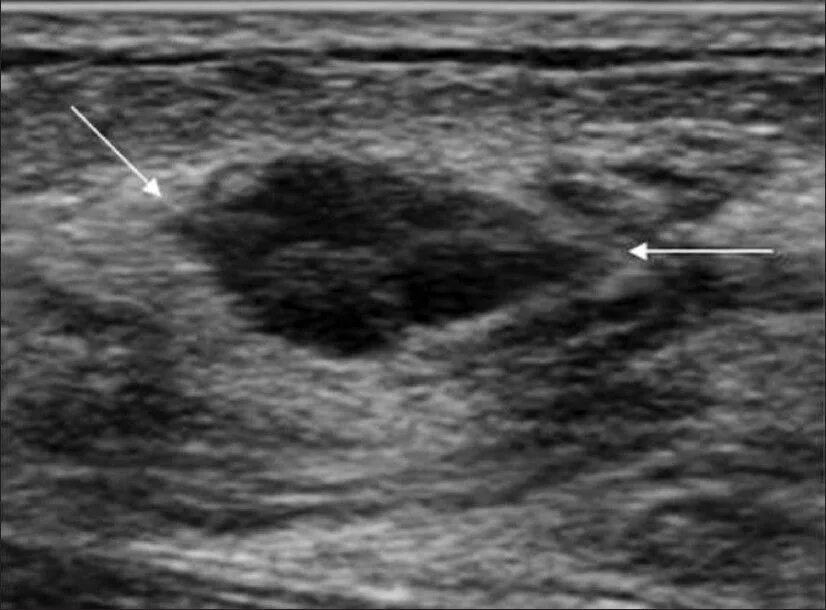

Как выглядит фиброаденома молочной железы